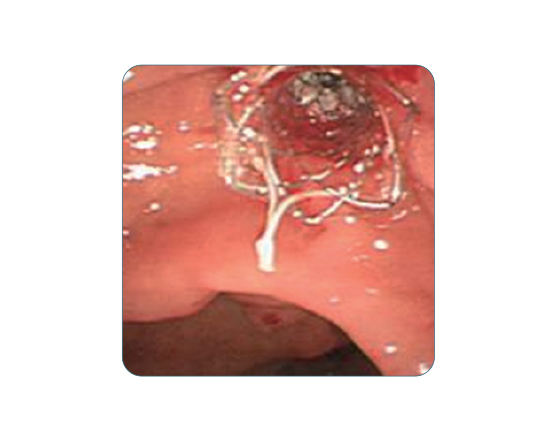

Bumpy yapısı sayesinde migrasyon riskini en aza indirir. Safra yolu darlıklarında etkili bir çözümdür.

Kaplı yapısı doku içi büyümeyi engeller. Uzun vadeli kullanım için uygundur.